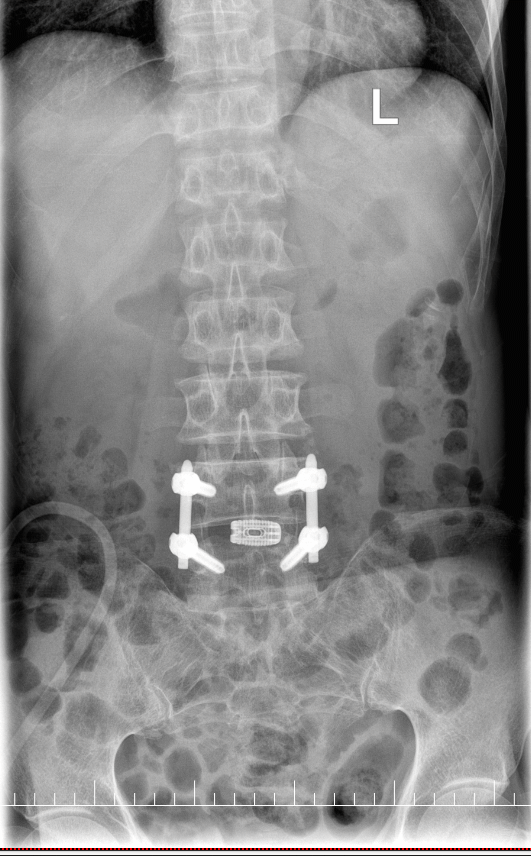

术后复查

术后,在医护人员的精心护理和康复指导下,黄先生的恢复情况超出了预期。术后第一天,他就能在床上进行简单的肢体活动,腰部及下肢的疼痛麻木感明显减轻。术后第三天即可下床行走,照片中的他,已经能自主行走,虽然步伐还不算太快,但相比术前的艰难行走,已经有了天壤之别。

手术首先采用经皮椎弓根螺钉固定技术,通过几个微小切口植入椎弓根螺钉,为脊柱提供稳定支撑。医生在高清影像设备引导下精准操作,每个步骤都准确无误。

最后,植入3D打印椎间融合器完成融合。这种融合器根据患者解剖结构个性化定制,表面特殊纹理能更好地与骨组织结合,大大提高了融合成功率。